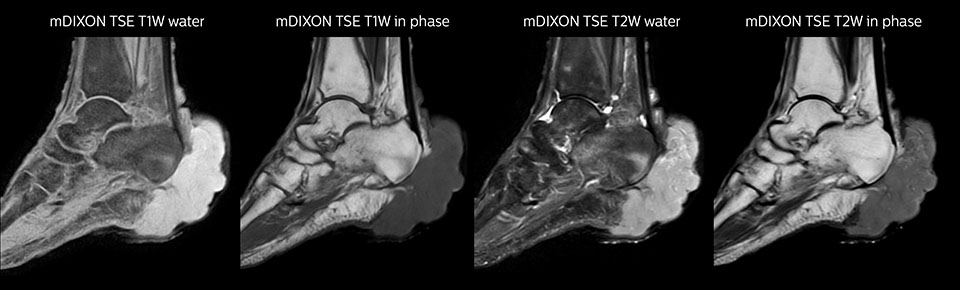

mDIXON TSE of ankle

MRI examination on Prodiva 1.5T of a 72-year-old female with a malignant melanoma in the ankle. mDIXON TSE provides excellent fat suppression, without the distortion that is often seen at such extremities.